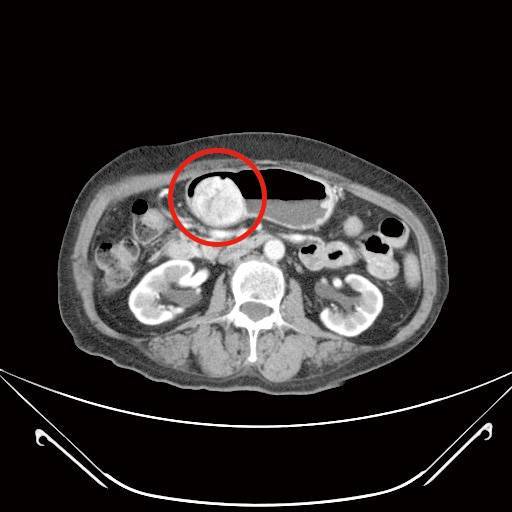

胃腸道基質瘤(上圖)

胃腸道基質瘤(GIST),是由腸胃道肌肉層的間質細胞長出來的惡性腫瘤,佔所有腸胃道癌症的2%左右,好發於年長病人,且年齡約在65-69歲,但也有不到2%的機率發生在20歲以下年輕病人(多與基因遺傳有關)。據跨國統計顯示,在香港、台灣、韓國與挪威有較高的發生率,約每百萬人有19-22人,美國及加拿大的發生率約每百萬人有7-8人。

胃腸道基質瘤在腫瘤還小時,鮮少有症狀,通常有症狀時多已大於2公分,由於臨床症狀沒有特異性,常見如腹部脹悶不適、噁心嘔吐、大便出血、體重減輕及排便習慣改變等,依照腫瘤生長位置不同而有不同的臨床表現。